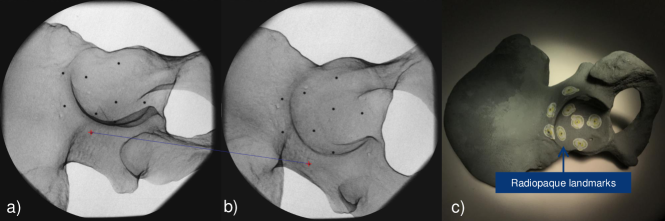

Tracking accuracy is computed by acquiring X-ray images from a phantom with several radiopaque landmarks and measuring the stereo error between the corresponding landmark points in different images.

The phantom is constructed by attaching 9 radiopaque mammography skin markers (bbs) with diameters of 1.51.51.5 mm, inside and near the acetabulum on a pelvis model as shown in Fig. 5. Next, we acquired 11 X-ray images from 50superscript50-50^{\circ} to +50superscript50+50^{\circ} along C-arm oblique rotation, and 9 X-ray images from 40superscript40-40^{\circ} to +40superscript40+40^{\circ} on the cranial/caudal direction, with intervals of 10superscript1010^{\circ}. In the planning software, we placed a virtual sphere with the same diameter as the bbs on each of the bb landmarks, and measured the distance of the bb in the second image to the epipolar line from the center of the corresponding virtual sphere in the first image. The error distance is measured as 7.58±3.02plus-or-minus7.583.027.58\pm 3.02 pixels444values reported as mean ±plus-or-minus\pm standard deviation in an X-ray image with pixel size of 1024×1024102410241024\times 1024 and pixel spacing of 0.220.220.22mmpixelmmpixel\frac{\text{mm}}{\text{pixel}}. In addition, we acquired a cone beam CT (CBCT) scan of the phantom and measured a root mean square error of 1.371.371.37 mm between the bbs in the CT and those reconstructed using two X-ray images.

Refer to caption

Figure 5: The geometric error is measured using radiopaque bbs viewed in the stereo X-ray images (a-b). The blue line highlights a pair of corresponding bbs in the two images. The phantom is shown in (c).